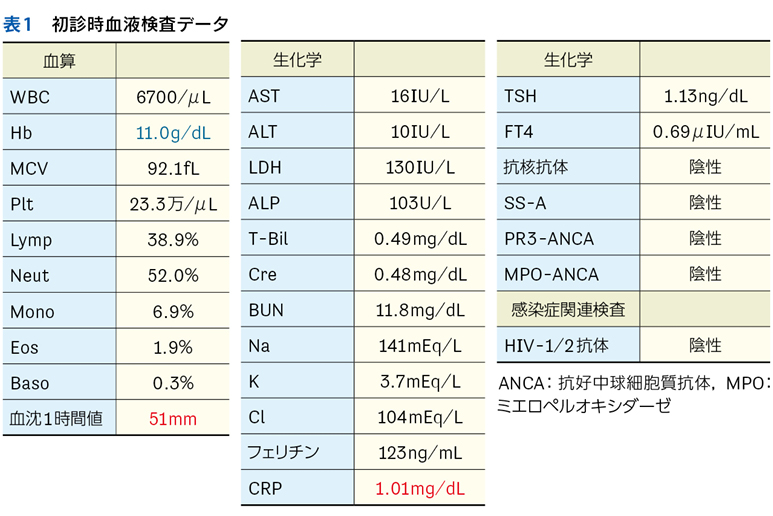

Case 1

独居の高齢者が自宅内で倒れている状態で発見され搬送された。最終健常は5日前。頻脈,SpO2低下,意識障害,感染徴候を伴う褥瘡,急性腎障害,高ナトリウム血症,クレアチンキナーゼ高値,炎症反応亢進,膿尿がみられている。

▶ この患者は何らかのイベントを契機に動けなくなり,長時間倒れていたものと推測される。多数ある「プロブレム」の中には,最初のイベントに直接起因するものもあるかもしれないが,大部分は倒れていた結果として生じてきたもの(最初のイベントの診断という観点では「ノイズ」)だろう。こういった患者が「脱水症」とか「横紋筋融解症」としてのみ治療されているケースをよく見かけるが,これは表層に現れた二次的,三次的な現象を取り上げているだけであり,最初のイベントの鑑別と治療が本来必要である。

Case 2

1カ月続く発熱と消耗のため入院している患者。発熱当初から変更を繰り返しながら抗菌薬が使用されており,現在も2剤併用中。ほかにも対症療法などで複数の薬剤を使用中。血液培養は抗菌薬使用開始後2週間で採取され陰性。経過中,皮疹,肝機能異常,腎障害,汎血球減少が出現している。

▶ こちらは初期評価不十分のまま多数の介入がなされたケースである。患者が呈している「プロブレム」をまとめて,「皮疹,肝機能異常,腎障害,汎血球減少を伴う遷延性発熱」とフレーミングし,たとえば血管内リンパ腫や血球貪食を伴う成人スティル病などを考えることも可能だが,現在の症状や検査異常(の一部)は抗菌薬をはじめとした介入の副作用として生じているのかもしれない。すべてのプロブレムが一元論で説明されない可能性も考慮したフレーミングも用意するのが謙虚な態度だろう。